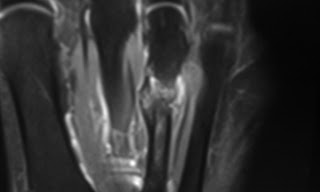

Stress fracture in a suspected Morton 's neuroma